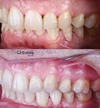

Diş Çapraşıklığı